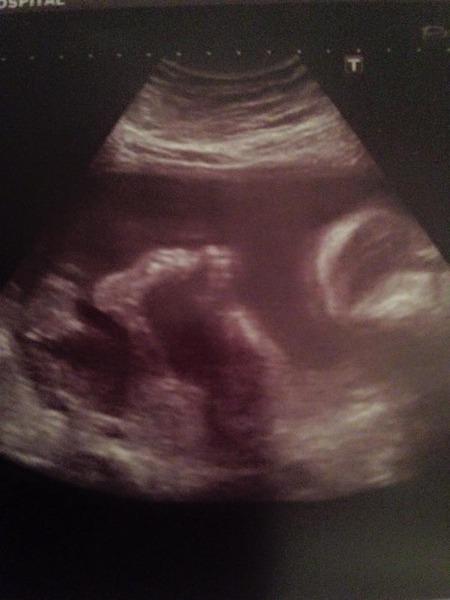

Well my scan was good although the little tinker was not overly cooperative and was more interested in showing us his new trick of touching his toes than lying in a better position for measurements to be taken. So it turns out that I get a bonus scan in two weeks time to complete the measurements checklist, which is quite nice! All looks well and they don't have any concerns. Here is a pic of our little monkey playing with his feet - also posted on FB. Hope everyone else's scans go well x

croon great news, lovely scan pic!

Croon - what a lovely picture. Lovely show-off baby. Grin